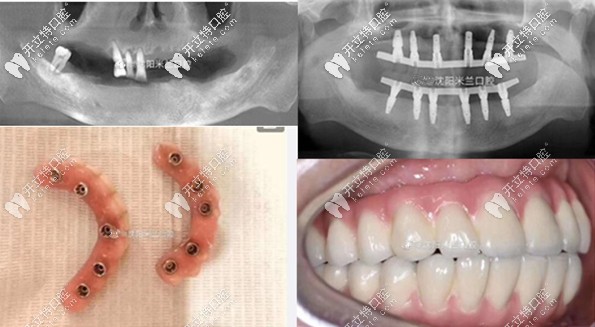

沈陽(yáng)米蘭口腔全口種植牙案例

沈陽(yáng)米蘭口腔種植牙案例賞析

張叔缺牙10多年了,慕名來(lái)到沈陽(yáng)米蘭口腔,采用方式:全口種植即刻戴牙,當(dāng)天種牙當(dāng)天用牙,種完后非常滿(mǎn)意,開(kāi)心的像個(gè)孩子。

沈陽(yáng)米蘭口腔種植牙采用,三維設(shè)計(jì)軟件規(guī)劃植體,設(shè)計(jì)并生成數(shù)字化種植導(dǎo)板,當(dāng)天種植當(dāng)天用。